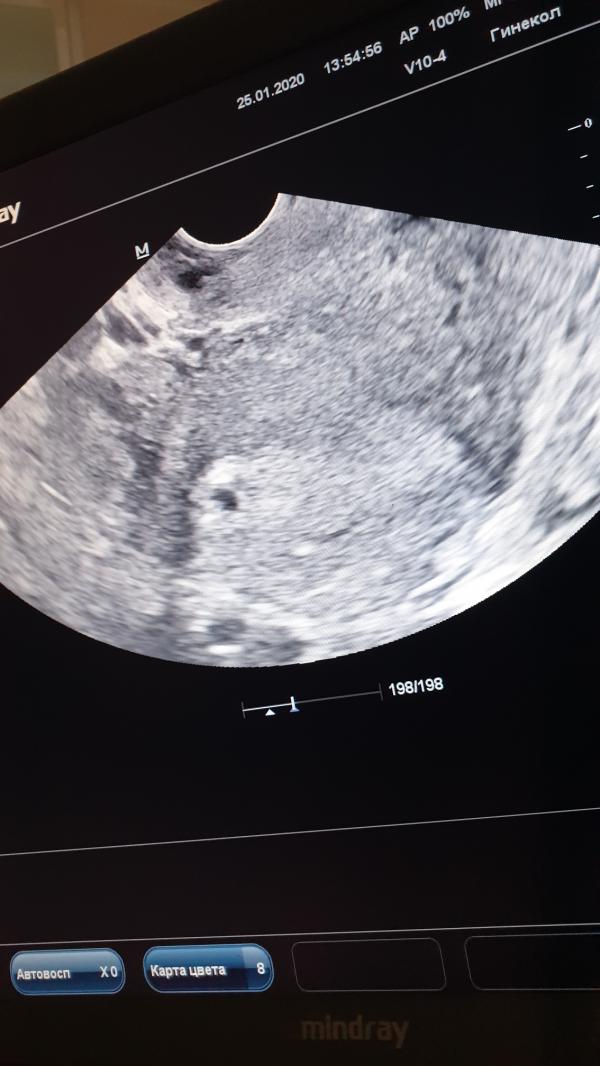

Выписали меня вчера из больницы, по итогу утреннего обхода-осмотра. Сделали УЗИ нашли плодное яйцо 7мм, мои жалобы на мазню бежево-кофейного 😁🤦🏻♀️цвета, (выделения то светлее, то темнее, то больше,то меньше) их вообще не смутили и они никак их не прокоментировали🙄🤦🏻♀️Вообще у меня эрозия была до беременности, на мой вопрос им....может это эрозия? Врач: а до беременности была такая мазня? Нет?! Ну значит это не она! 🙄 если бы была по УЗИ отслойка или еще что-то они бы увидели?! 🤦🏻♀️ просто у меня при таких выделениях ничего не тянет,не болит. Или при угрозе может быть просто мазня без боли? 🙄 Пью дюфастон 2т/2р в день, и транексам по 1т×3р 3-5дней🙄 короче хз, нервов не хватает🤦🏻♀️ вообще во время лапараскопии они мне левый яичник от спаек очистили, разсекали их наверное,может оттуда сукровица эта выходить через матку? 🙄я уже реально не знаю,какую причину найти